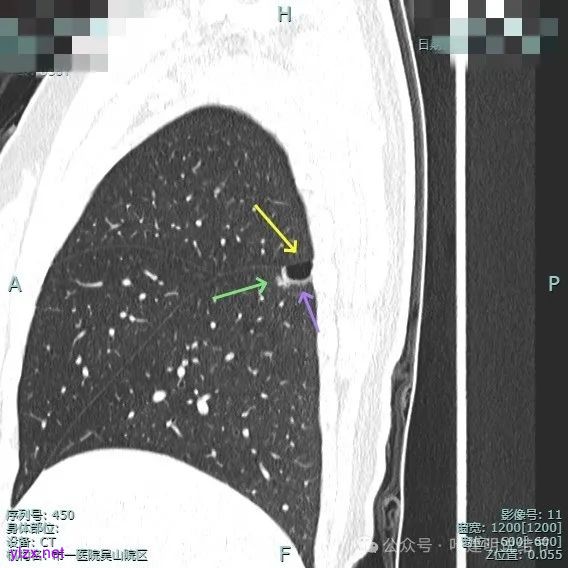

囊壁里面也有小空泡征。

混合密度但还是太致密,内壁毛糙不平。

病灶轮廓清楚,囊壁厚薄不均,贴着叶间裂与胸膜。

1、诊断问题:这是很典型的囊腔型肺癌,符合我自己之前提出的囊腔型肺癌三要素:(1)囊壁厚薄不均;(2)血管进入囊壁;(3)囊腔内壁不光滑(或再加止整体轮廓与边界较清)。而且由于囊壁实性成分明显,所以是有风险的,要及时干预处理。